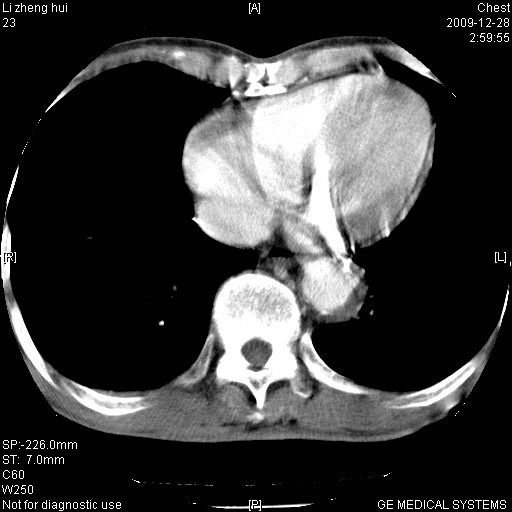

男  79岁 胸部痛急诊入院,晚上做的增强

考虑主动脉瘤?(增粗、钙化、壁血栓?)

动脉瘤伴附壁血栓

1)考虑胸主动脉壁间血肿或夹层动脉瘤。2)多发性肝囊肿。

1)考虑胸主动脉附壁血栓或夹层动脉瘤。2)多发性肝囊肿。